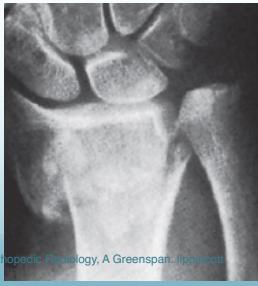

Common Fracture Sites ✓

- Colle’s fracture (distal radius)